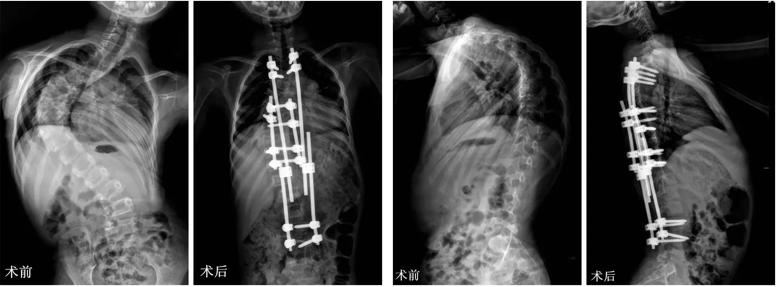

手术治疗:

矫正融合手术: